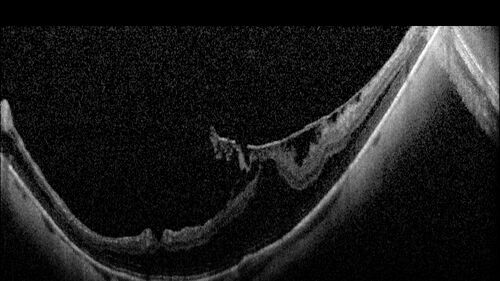

Stable Myopic Tractional Maculopathy

73 year old female with mild vision loss from table myopic tractional maculopathy in the left eye